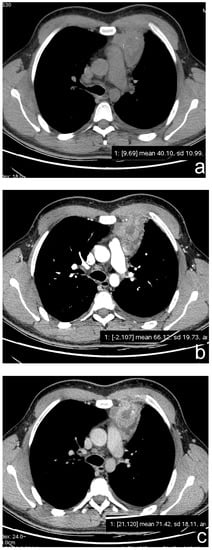

Sakai S. et al. [44] investigated the potential role of DCE-MRI for differential diagnosis of anterior mediastinal tumors in 59 patients with 31 thymomas, 14 thymic carcinomas, 7 lymphomas, 4 germ cell tumors and 3 thymic carcinoids. Post-contrast sequences were performed in the axial plane at 30 s interval for 5 min. Similar to Yabuuchi H. et al., these authors found that thymomas had an early enhancement peak with a following wash-out. All the other lesions, including thymic carcinomas and carcinoids, had a later peak (1.5 ± 0.9 min for thymomas vs. 3.2 ± 1.2 min for other lesions) (Figure 4).

Figure 4.

(a–c) A 23-year-old man with a partially cystic lesion of the anterior mediastinum. CT scans without contrast (a) and after contrast medium administration in arterial (b) and delayed (3 min, (c)) phases show late enhancement peak of the solid component (ROI 1). Surgery revealed a seminoma.

However, no significant difference was found between different histological subtypes of thymoma.